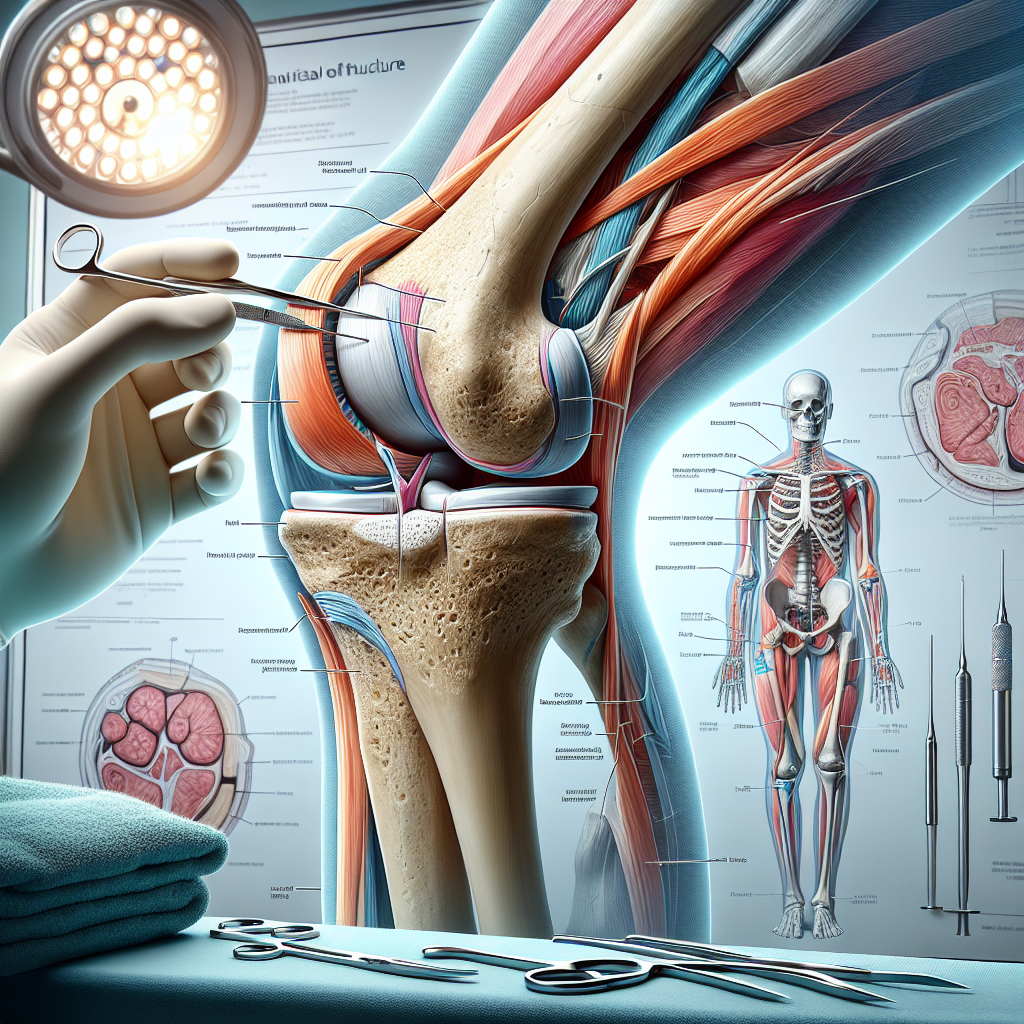

A fracture of the medial femoral condyle involves a break or crack in the end of the femur, located in the knee joint. This part of the femur, along with the tibial plateau, forms the knee joint. The medial condyle is situated towards the inner side of the leg, closest to the midline of the body. Recognizing the importance of this structure is vital, as any misalignment during healing can lead to long-term complications such as arthritis due to the rough spots that develop from improperly healed cartilage.

When discussing the necessity of surgery, Dr. Guyer stresses that precise alignment of the bone is imperative. A displacement can cause improper healing and result in a misaligned articular surface, leading to accelerated wear of the knee cartilage and potential future osteoarthritis. Therefore, surgical intervention generally involves using plates and screws to realign and stabilize the fracture.